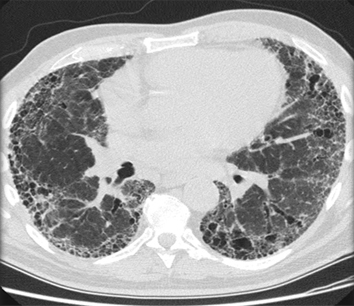

Chest CT showing idiopathic pulmonary fibrosis

From the personal collection of Dr J.C. Munson, Center for Clinical Epidemiology and Biostatistics, University of Pennsylvania School of Medicine